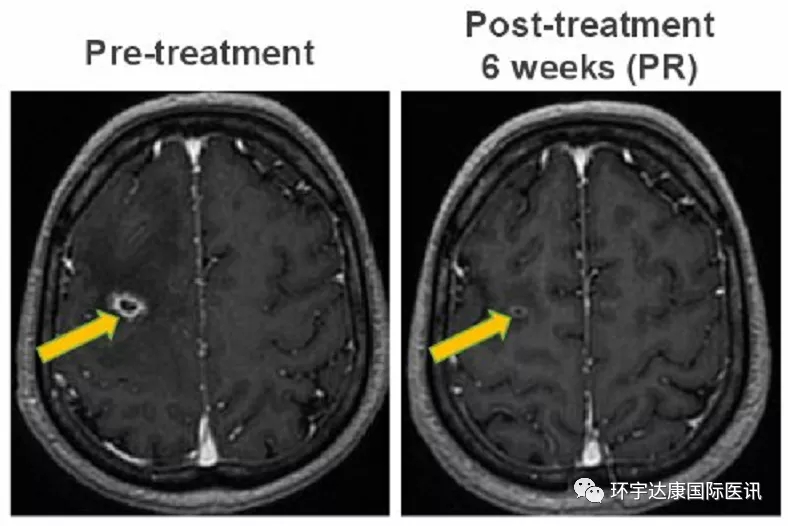

1、强效抗脑转

一位49岁的男性患者,确诊为ROS1阳性非小细胞肺癌,既往接受了化疗和克唑替尼的治疗后病情进展,出现脑转移。接受Taletrectinib(600mg,QD)治疗后迅速出现响应,第6周的影像学检查显示脑部转移病灶明显缩小,达到部分缓解状态(PR)。